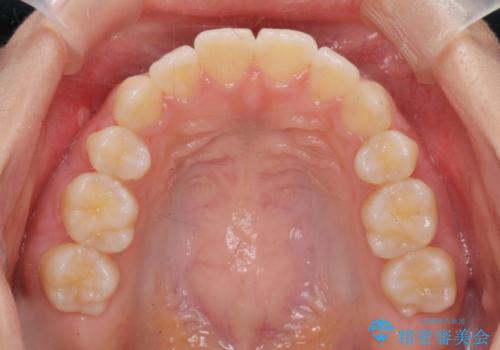

- 5年前にワイヤー矯正治療を終了したが、突き出たように見える前歯の仕上がりが気に入らず、再矯正治療を希望され来院されました。

マイクロインプラントを用いた遠心移動とIPRを行うことによる前歯の突出感の改善をマウスピース矯正治療で計画します。

突出していた前歯の角度が大きく改善し、審美的な仕上がりに満足いただくことができました。